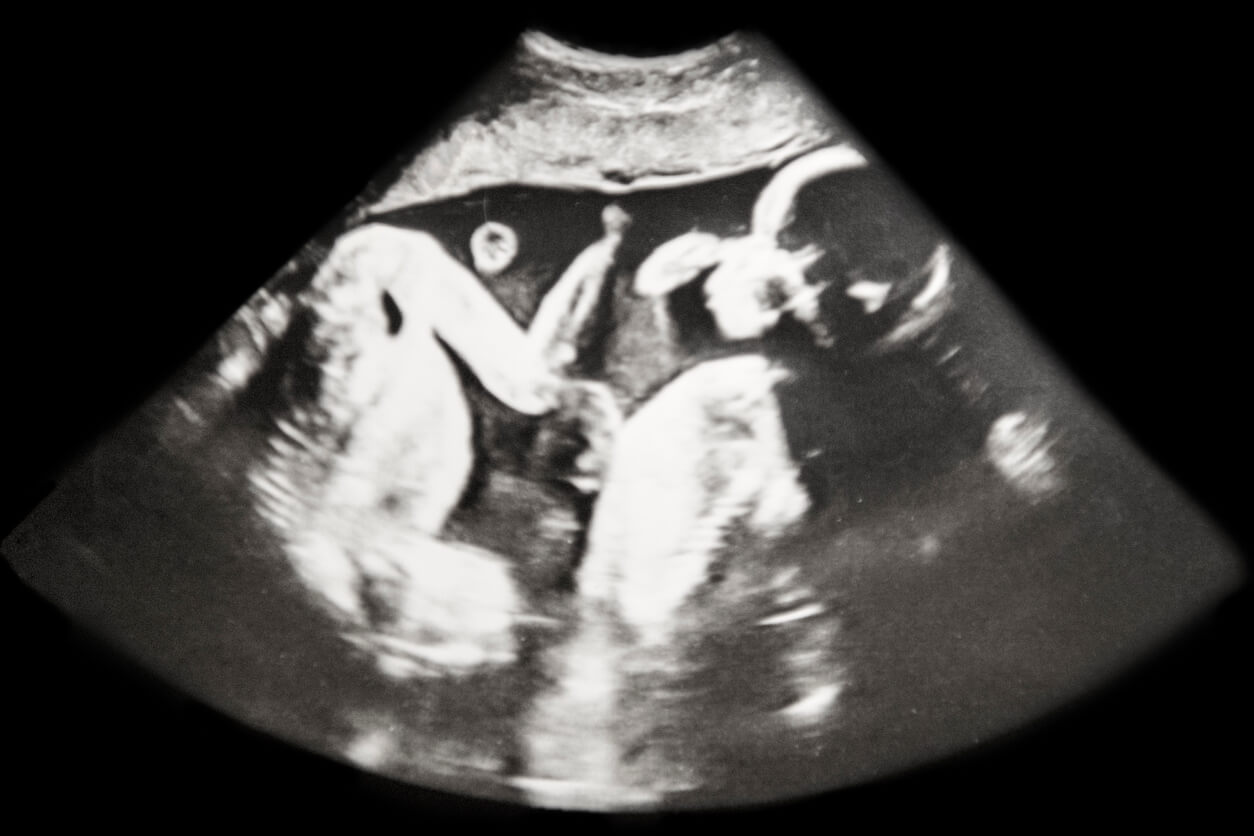

En ocasiones, es posible identificar el tipo de embarazo múltiple desde los primeros meses de gestación. Pero en otros casos, hay que esperar hasta el nacimiento. De todos modos, hoy te enseñaremos sus diferencias.

Durante la gestación, los profesionales suelen fijarse en las estructuras que comparten ambos embriones a fin de determinar el tipo de embarazo múltiple en curso.

En el caso de los gemelos bivitelinos, cada embrión se implanta de forma independiente en el útero materno. Por ende, cuenta con su propia placenta y su propia bolsa amniótica.

El caso de los gemelos univitelinos, la situación es algo más compleja y, según el momento en que ocurre la división del huevo, pueden darse tres escenarios:

- Cuando la división ocurre en los tres días posteriores a la fecundación, cada embrión desarrolla su propia bolsa amniótica y su propia placenta.

- Si la división ocurre entre el cuarto y el séptimo día, los bebés comparten placenta, pero cada uno crece en su propia bolsa amniótica. Esta es la condición más frecuente, la cual ocurre en el 90 % de los casos.

- Cuando el cigoto se divide entre 7 y 13 días posteriores a la fecundación, los gemelos comparten tanto la placenta como la bolsa amniótica. Es en estas circunstancias, pueden surgir complicaciones a futuro, como el desarrollo de gemelos siameses, o en el síndrome transfusor-transfundido.